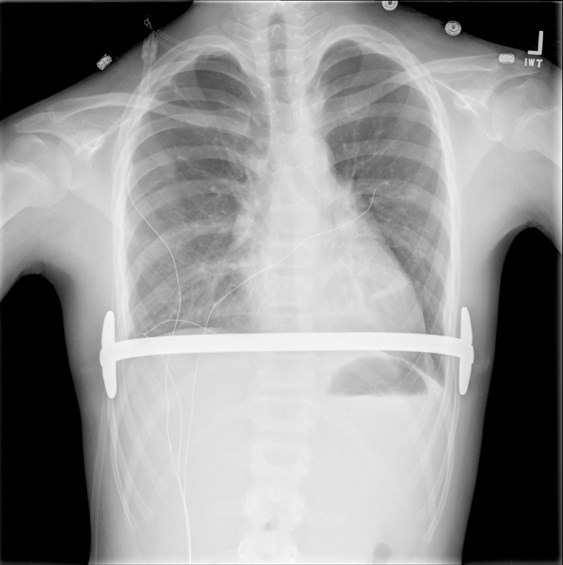

پکتوس اکسکاواتوم یک اختلال مادرزادی است که باعث می شود قفسه سینه ظاهری فرورفته یا غار شکل پیدا کند. این شایع ترین ناهنجاری مادرزادی دیواره قفسه سینه در کودکان است.

بدشکلی های دیواره قفسه سینه یا رشد و ظاهر غیر طبیعی قفسه سینه می تواند از خفیف تا شدید متفاوت باشد. این بد شکلی ها مادرزادی هستند و ممکن است در بدو تولد یا بعد از آن در کودکی آشکار شوند. صرف نظر از این، شدت ناهنجاری معمولاً در دوران بلوغ به سرعت پیشرفت می کند.